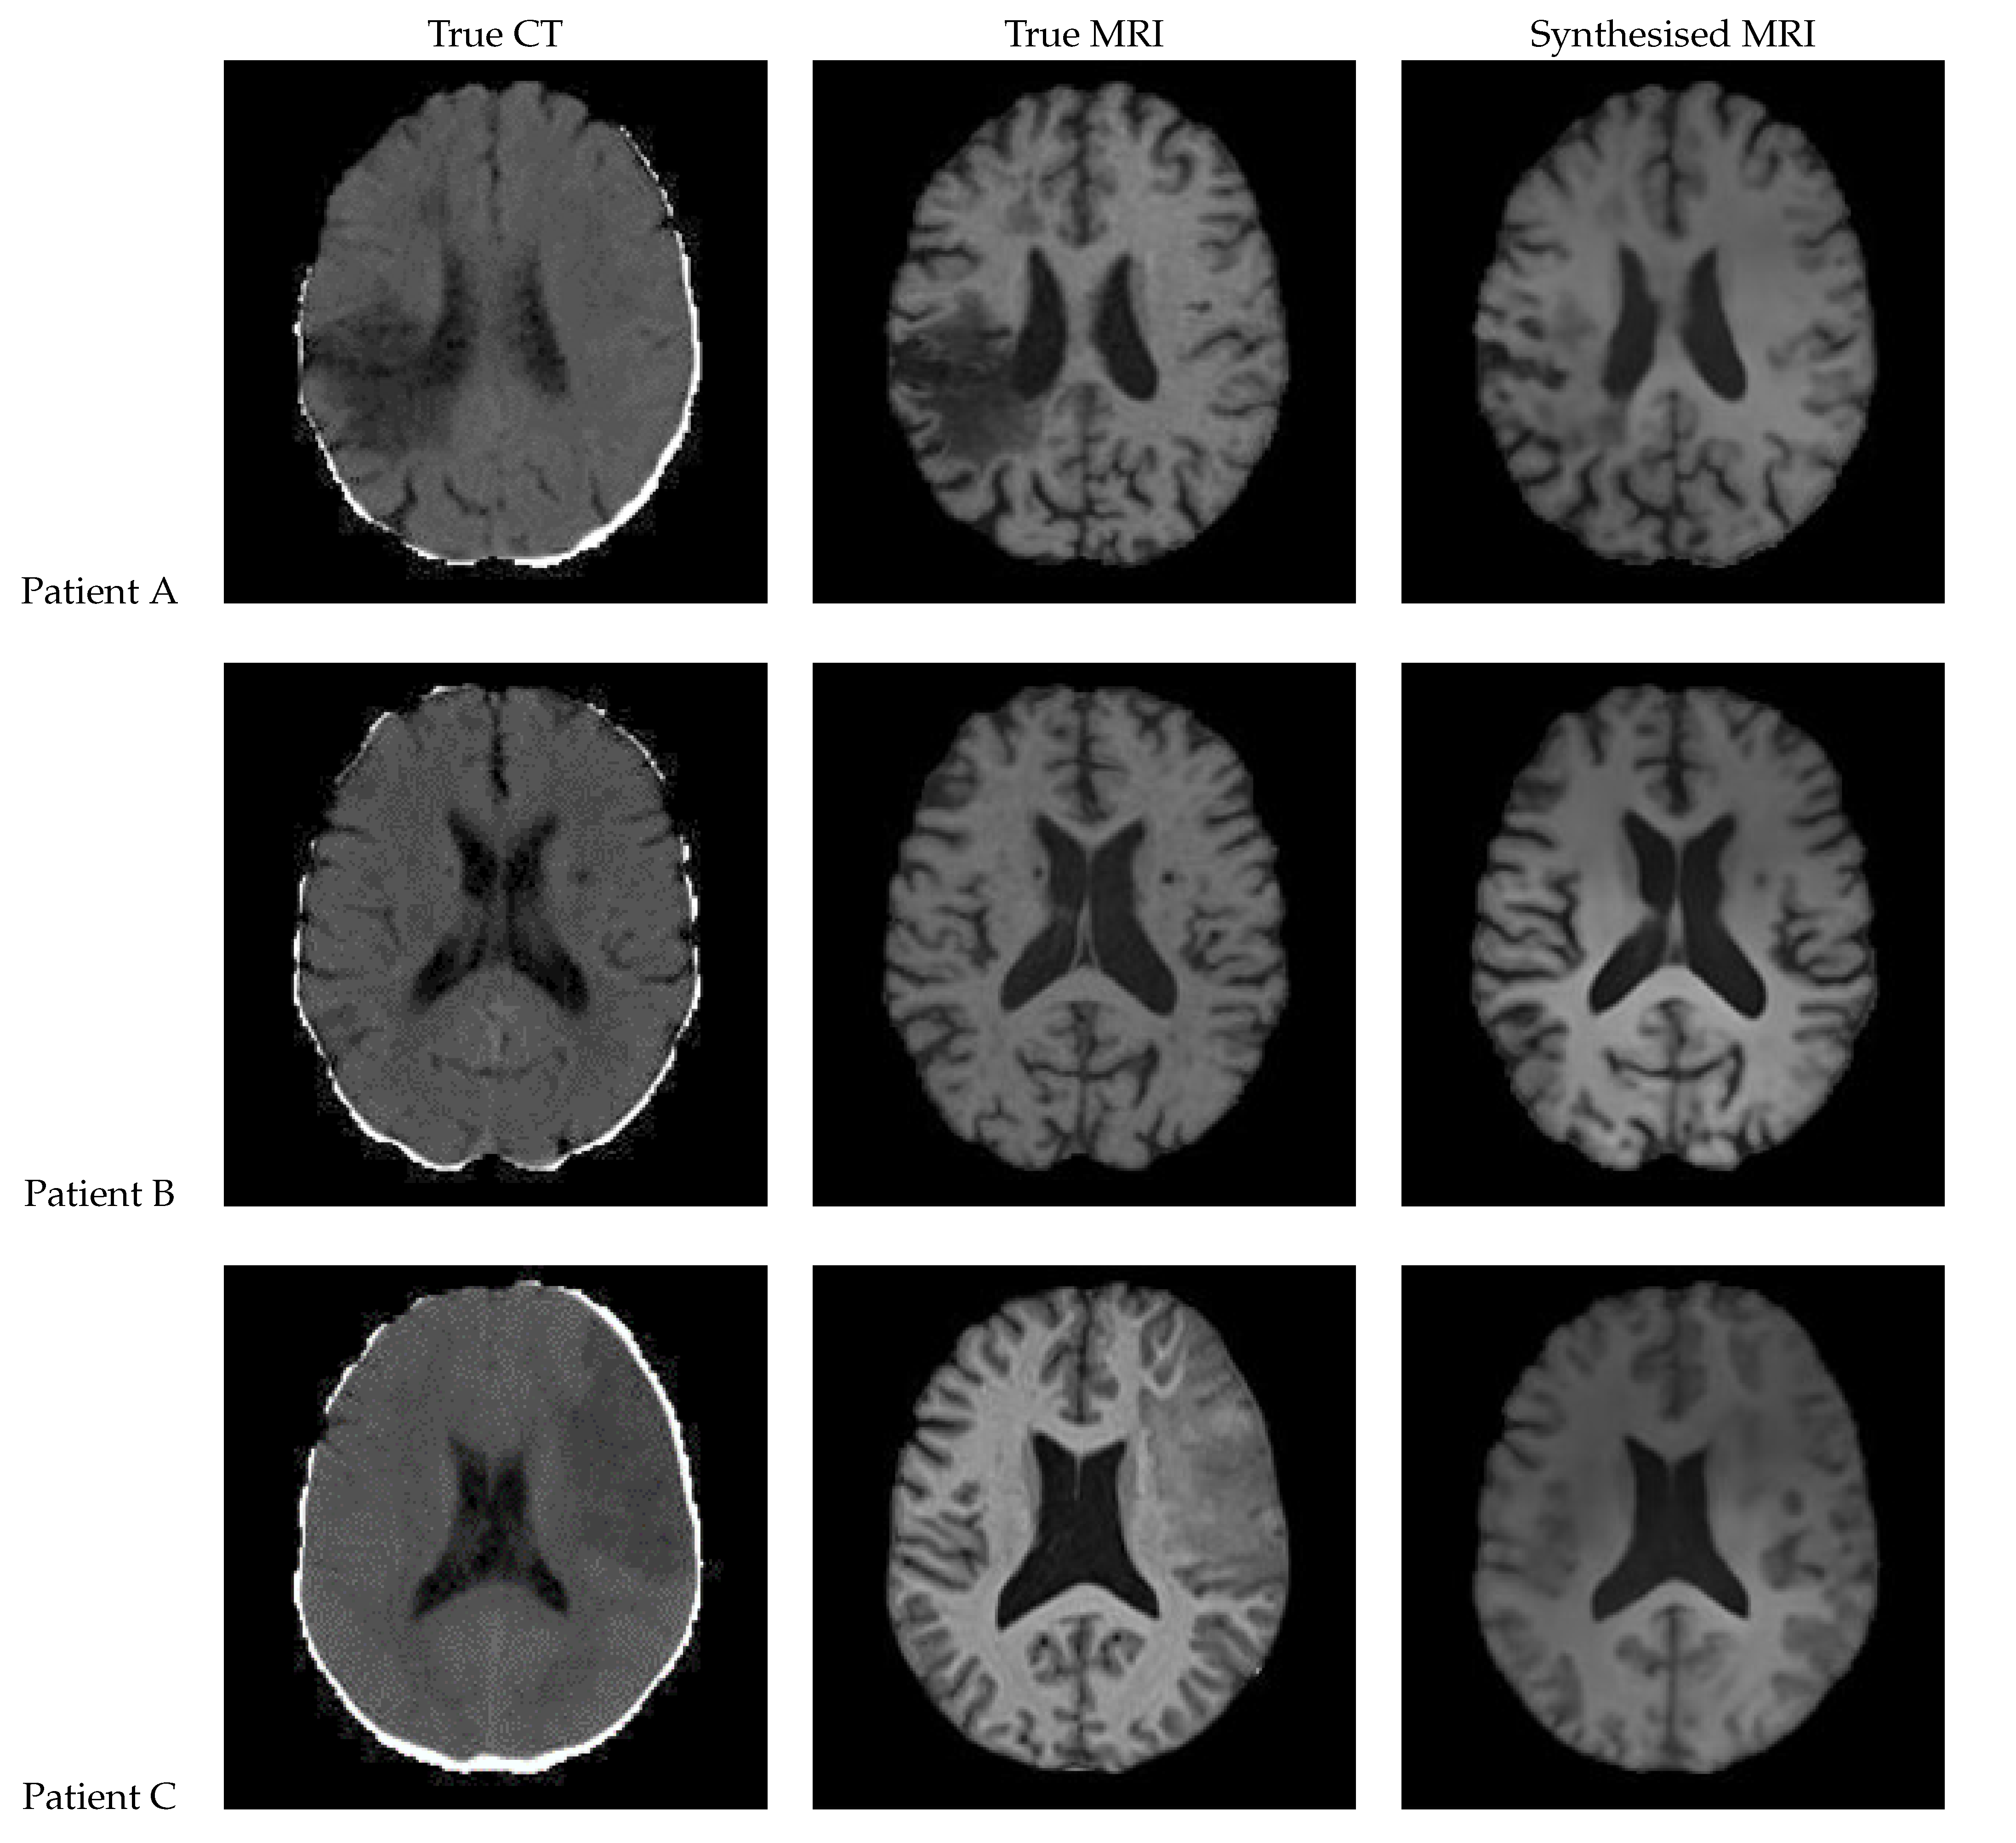

Figure 12 shows a sample slice of the synthetic MRI generated by a 3D UNet for three patients in the test set, along with the corresponding true MRI and CT slices. Patient A presents a large lesion, which can also be seen in the synthesised MRI, but with reduced contrast and less precise borders. Patient B shows a similar overall contrast to the true MRI. Patient C displays a very large, faint lesion that is not clearly visible in the synthetic MRI.

Figure 12. Axial slices of CT Scans (Left), True MRIs (Centre), and Synthetic MRIs generated by UNet (Right).